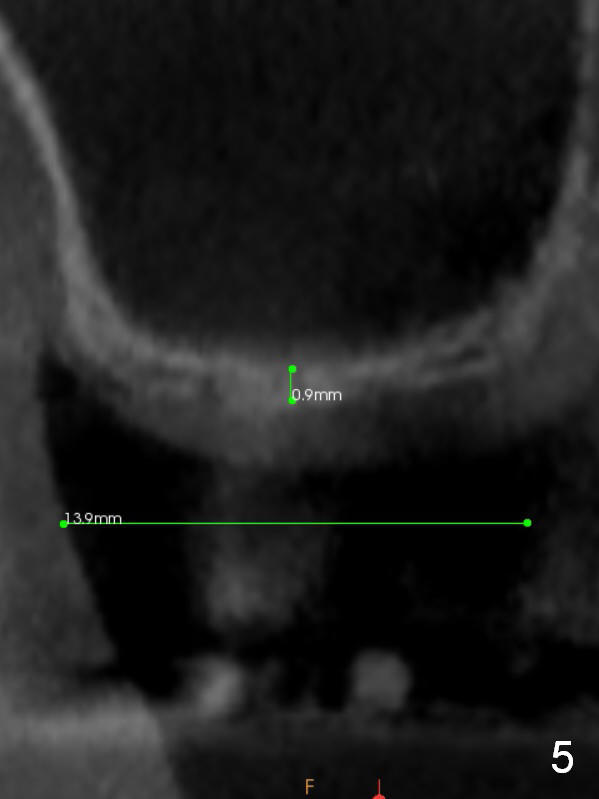

A 78-year-old man needs implant restoration at #2 in spite of limited bone height, because of severe ridge atrophy at #18 and 19. Sagittal (Fig.1-3) and coronal (Fig.4-6) sections show bone height less than 1 mm. If there is plenty of the keratinized tissue at #2, use a 4 mm tissue punch for access, followed by sinus lifter. Use fine and coarse allograft for sinus lift.